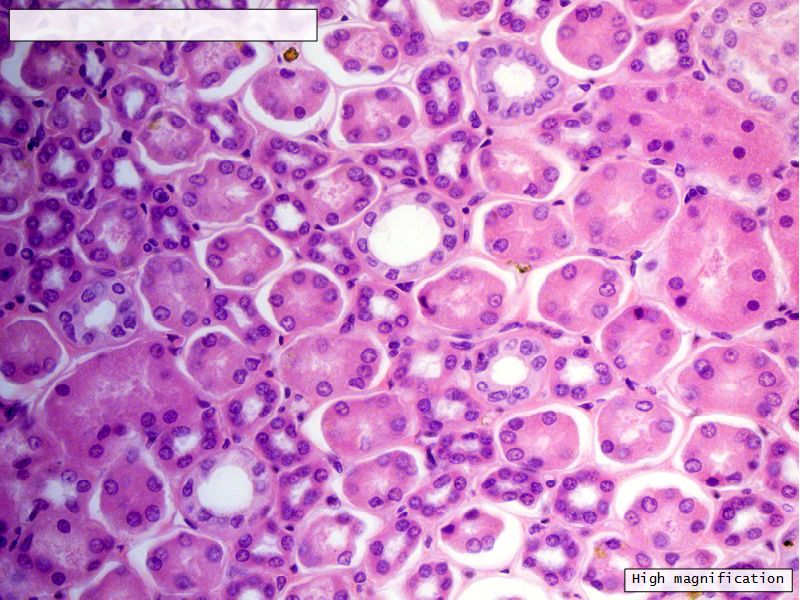

Appearance

- Cortex

- Renal corpuscles

- Convoluted tubules

- Medulla

- Loops of Henle

- Collecting tubules

Proximal convoluted segment

- Longest part of nephron

- Wide triangular cell

- Spherical nucleus

- Indistinct cell borders

- Luminal surface

- Striated brush border

Collecting tubule

- Cuboidal to columnar epithelium

- Distinct lateral borders

Main collecting ducts

- Wide lumen

- Pale staining columnar cells